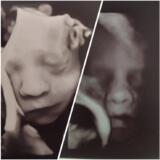

Ciao ragazze, io sono a 5+1, pochissimi sintomi e zero nausea.

Ho fatto le prime beta a 4+2 ed erano 775, ripetute a 4+4 con valore 1550 è l’ultima fatta ieri,sempre su indicazione della ginecologa, a 5457. Adesso la ginecologa non vuole che le rifaccio, mi ha rimandato direttamente all’ecografia. Ma sono sufficienti quelle che ho fatto? Come faccio a stare tranquilla da qui all’eco? Io sto continuando a lavorare e per lavoro mi muovo tanto in giro per Roma con i mezzi pubblici e a piedi, ho paura di fare qualcosa che possa fare un casino. Come mi regolo?